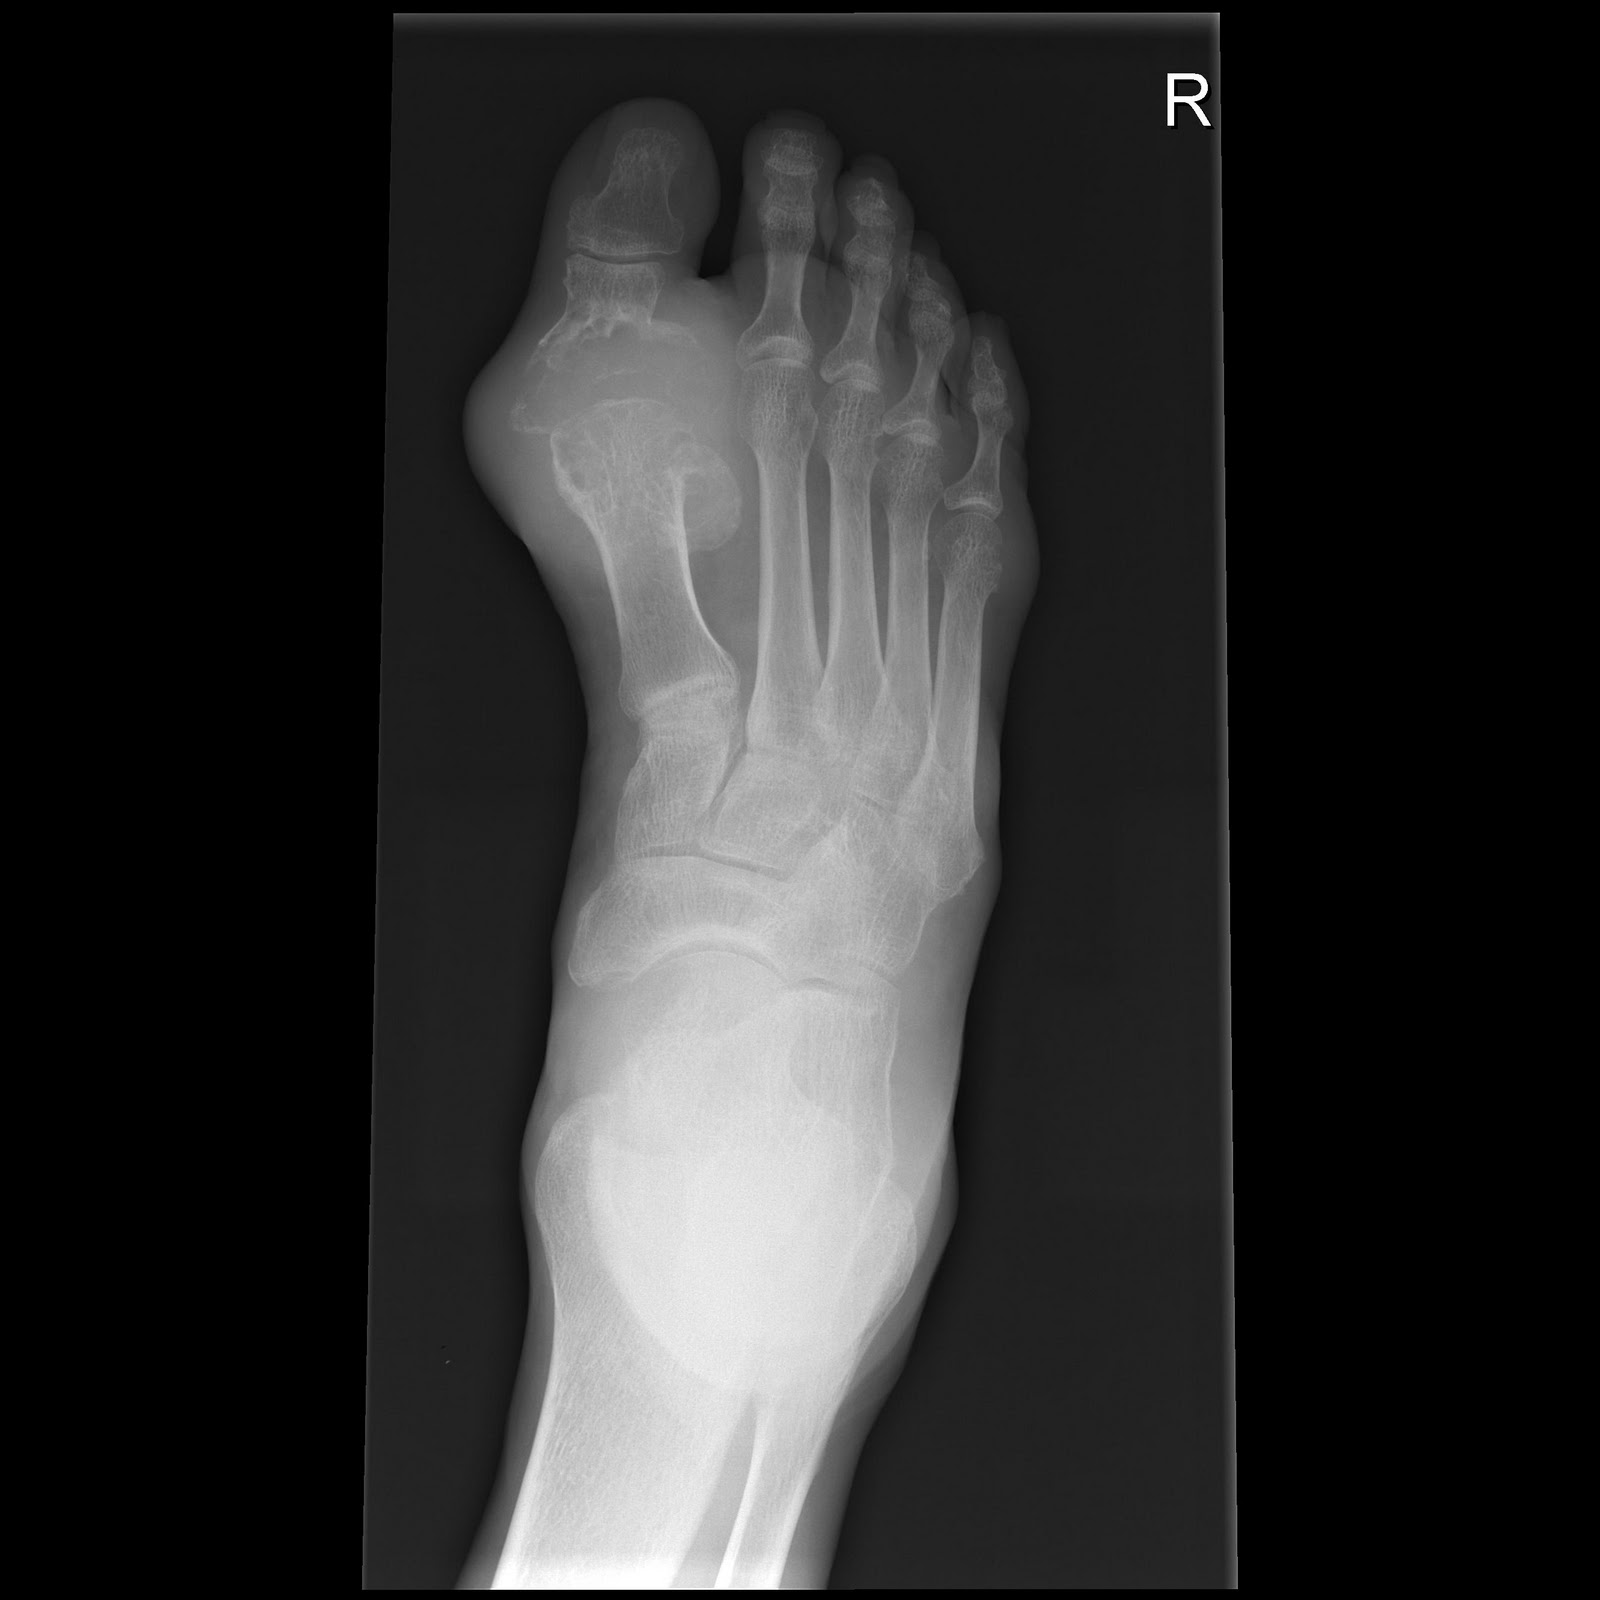

Scaphoid Fracture

PEARLS:

1. Scaphoid is the most commonly fractured carpal, followed by the Triquetral.

2. Three types:

a. Waist >70%         b. Distal pole           c. Proximal pole

3. Associated with avascular necrosis of the proximal pole (blood supply enters from distal end and flows proximally), and distal pole fractures have the worst prognosis.

4. Clinically, presents with snuffbox tenderness, more common in young adults, M>F.